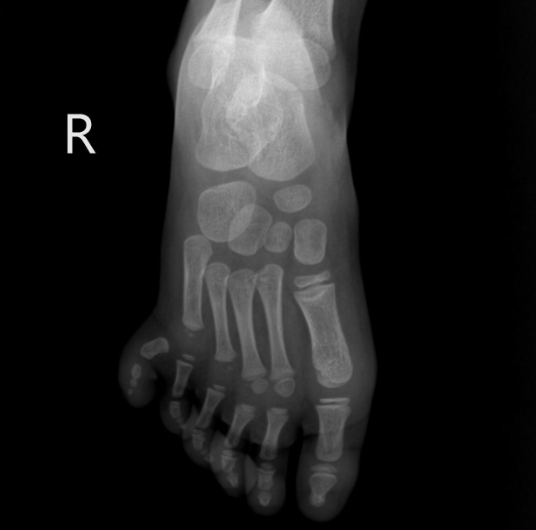

Ảnh chụp X-quang bàn chân phải của bé L. (Ảnh: BVCC)

Từ khi sinh ra, bé L. đã có một ngón thừa ở bên bàn chân phải. Cho rằng dị tật này không ảnh hưởng nhiều tới sức khỏe của L., gia đình không đưa em tới bệnh viện để kiểm tra sức khỏe. Chỉ đến khi dị tật được phát hiện và có sự tư vấn của bác sĩ, gia đình L. mới quyết định làm phẫu thuật cho em.